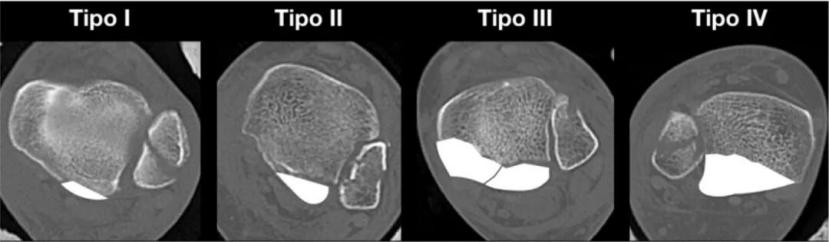

分型

踝关节骨折日益复杂,传统的X线片分型系统可靠性有限。基于多层螺旋CT三维重建的成像技术,能够精确描绘骨折形态。为此,本文采纳Bartonček等人提出的CT分型系统,该系统区分五种骨折类型,并为手术决策提供指导。

1 型:关节外骨折块伴完整的腓骨切迹。

2 型:延伸至腓骨切迹的后外侧骨折块。

3 型:累及内踝的后内侧两部分骨折块。

4 型:大的后外侧三角形骨折块(累及超过三分之一的腓骨切迹)。

5 型:不规则、骨质疏松性骨折块。

image.png

图1. Bartonček等人于2015年描述的基于CT的PMF分类